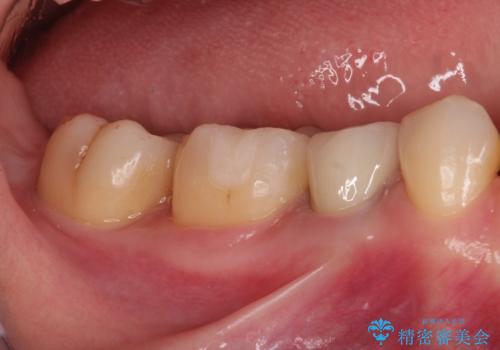

- 笑った時に見える金属を白くしたいとのことでメタルフリーの治療を希望され来院されました。

根管治療を行なったのち、オールセラミッククラウンにて修復処置を行っております。

- 39万円費用は治療当時の料金となります